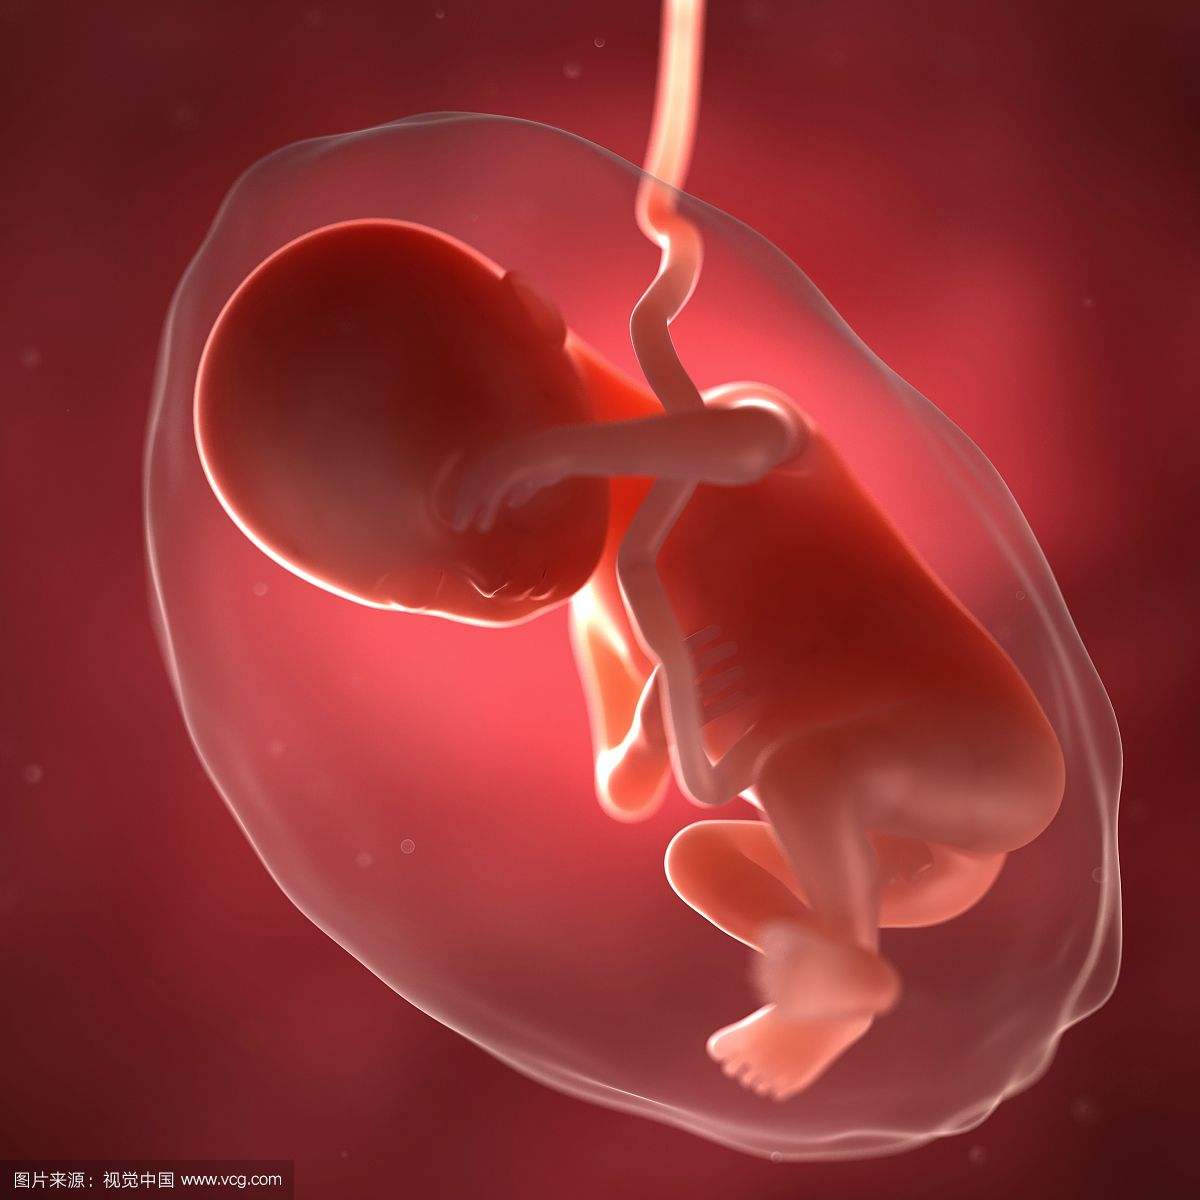

胎儿的变化

28周的胎儿现在坐高约26厘米,体重约1200克左右,这时的宝宝几乎占满了整个子宫,随着空间越来越小,胎动也在减弱。尽管胎儿现在肺叶还没有发育完成,可如果万一发生早产,胎儿在器械帮助下也可以进行呼吸。